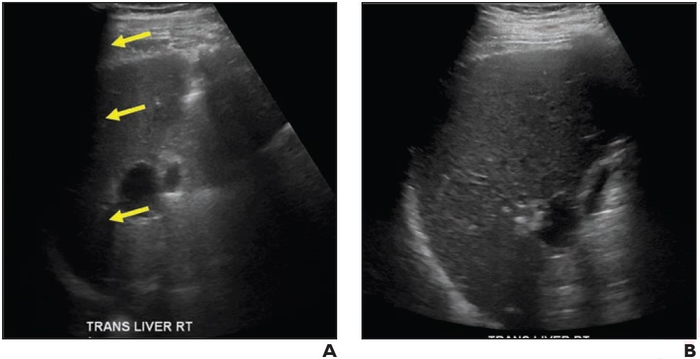

69-Year-Old Man With Chronic Hepatitis B

image: (A) Transverse gray-scale ultrasound image shows inability to visualize portion of liver. Examination received visualization score C. (B) Transverse gray-scale ultrasound image from examination performed 9 months later shows improved visualization of liver. Examination received visualization score A. view more